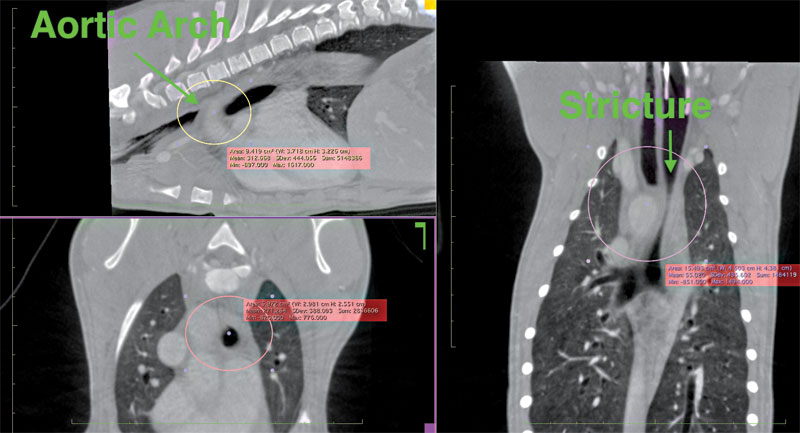

Another condition that can be seen in puppies is a PRAA, also known as a vascular ring anomaly (Figure 2). Birth defects also cause these and result in partial or complete rings forming around and squeezing the esophagus, trachea, or sometimes both. As the puppy grows, this issue becomes more apparent.

Figure 2. Evidence of a persistent right aortic arch (PRAA) in a one-month-old poodle puppy. Photo courtesy Imaginalis

The impact of these rings around the esophagus is not usually noticed until a dog starts eating solids, when the restriction often causes regurgitation of undigested food. Pressure also increases on the trachea as the dog gets bigger, leading to audible breathing problems.

This condition is the most disruptive of the three. An example of its impact was seen when a one-month-old poodle puppy was brought in because it was vomiting after every meal and was noticeably underweight compared to the rest of the litter. Diagnostic imaging found compression on her trachea and esophagus that would continue to impact her health. The condition would likely prove fatal if left untreated.

For example, after a veterinarian detected a PRAA on an HDVI CT scanner (Figure 3) and surgically removed it from a one-month-old poodle puppy, the patient caught up to the rest of the litter and is now living a normal life.

Figure 3. A PRAA detected by an HDVI CT scanner. Photo courtesy Imaginalis

The surgery required to remove any of the three abnormalities is intricate, especially with a PRAA, given its proximity to the esophagus and trachea. A complete, detailed image of the issue empowers veterinarians to perform surgery to the best of their ability and send as many patients as possible off to healthier lives.